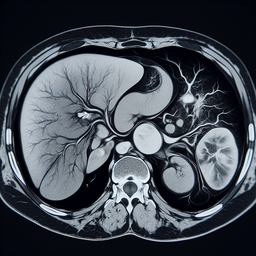

МРТ печінки

МРТ печінки – це неінвазивний метод діагностики, який використовує магнітне поле та радіочастотні імпульси для створення детальних зображень печінки та навколишніх структур.